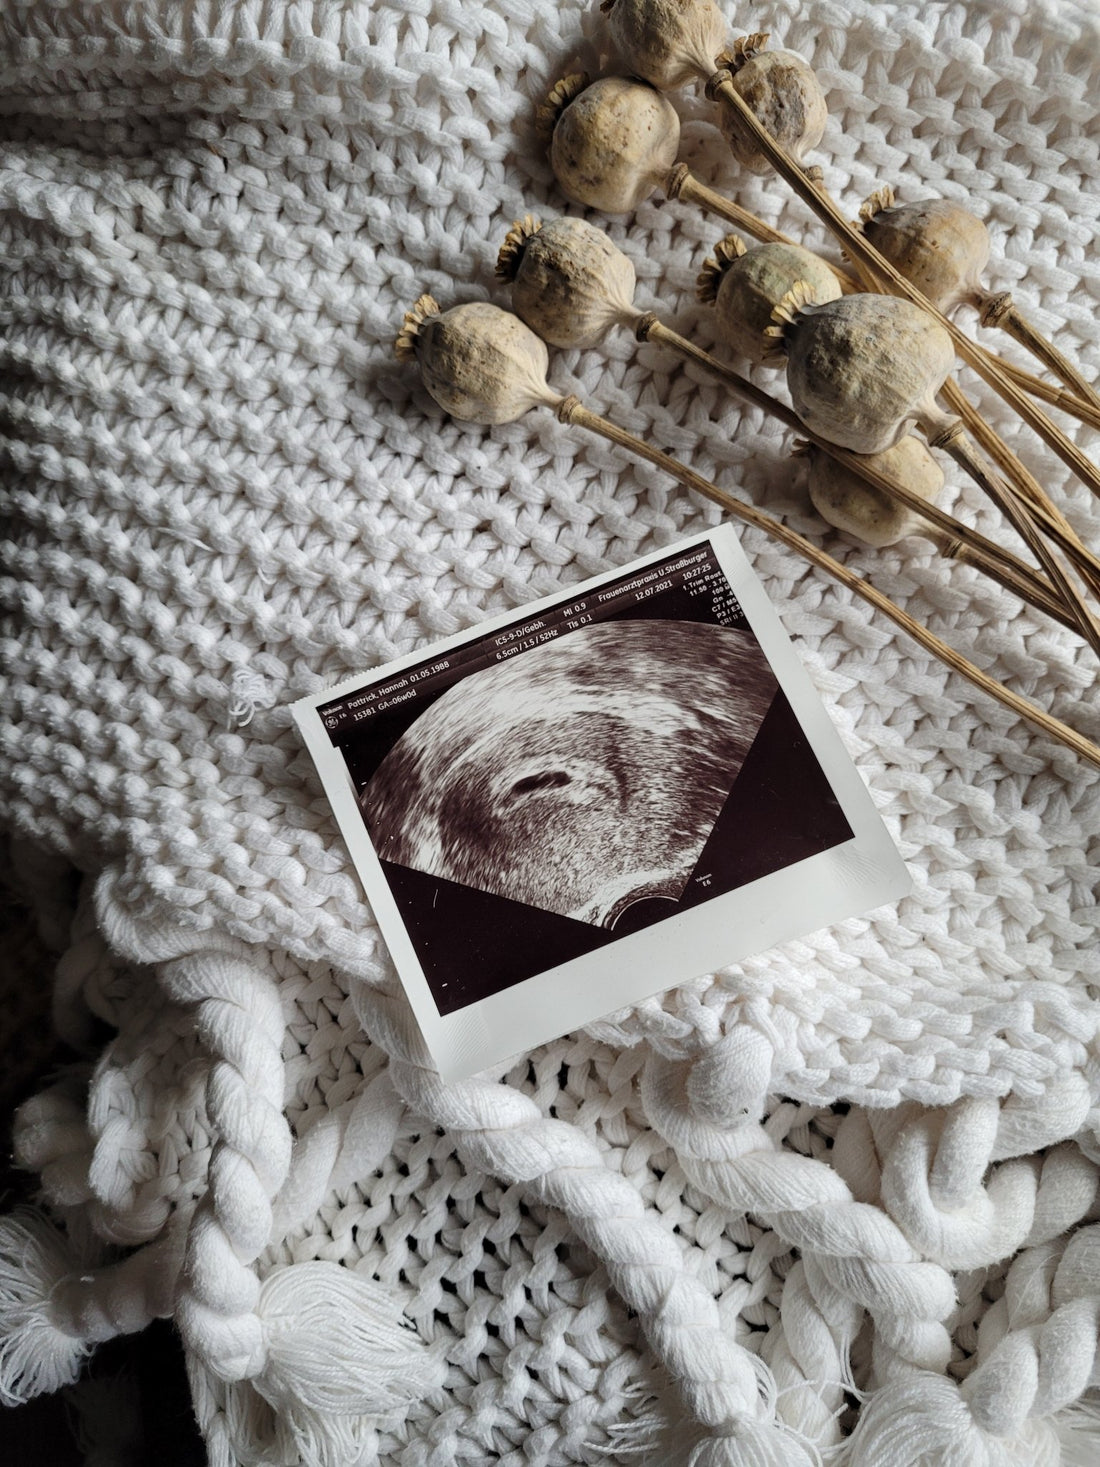

By Hannah Pattrick.

Putting our fears aside we took our first trip to the gynecologist to confirm the pregnancy and the care from there on out was incredible.